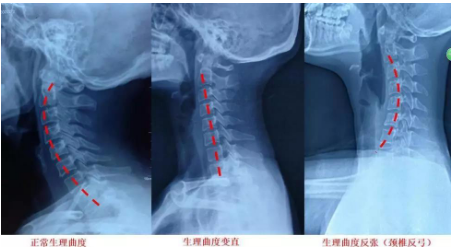

颈椎有7块互相堆叠的椎骨,这些椎骨构成了颈椎,正常的颈椎有个前凸的生理弧度,这就是颈部大楼的钢筋结构。

前面我们也说到了颈部的软组织协助维持着颈椎的正常生理弧度,当经常出现低头玩电脑看手机看书等情况,日积月累,颈部的软组织这些混凝土结构失去支撑功能,应力全部集中在大楼的钢筋结构上,久而久之,就容易出现老化甚至变形,这就是颈椎反弓,颈椎退变的主要原因。